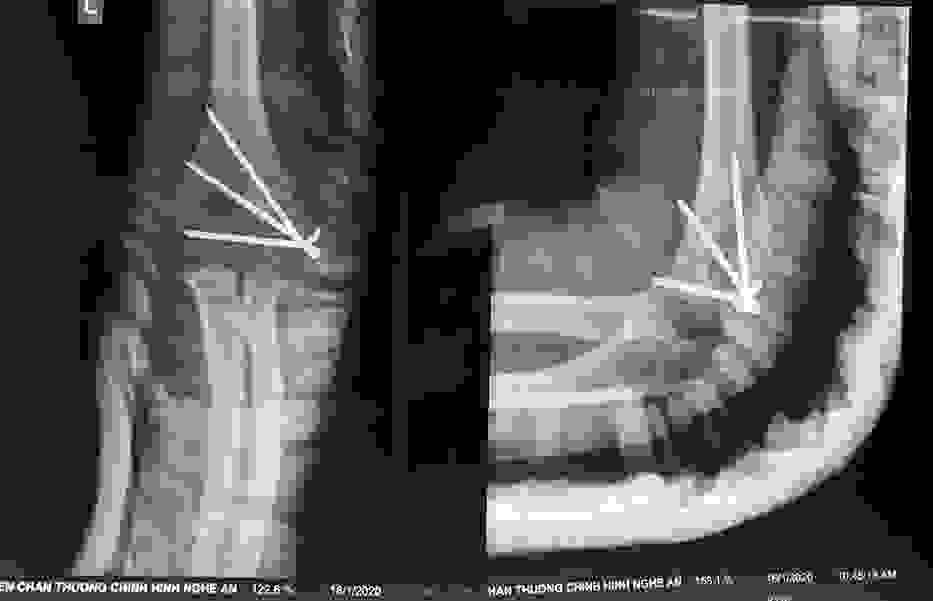

Phẫu thuật thành công ca bệnh hiếm gặp...khớp giả bẩm sinh xương chày

26/06/2019 17:00

Đã xem: 3381

Bệnh viện Chấn thương- Chỉnh hình Nghệ An, vừa phẫu thuật thành công cho bệnh nhi khớp giả bẩm sinh xương chày